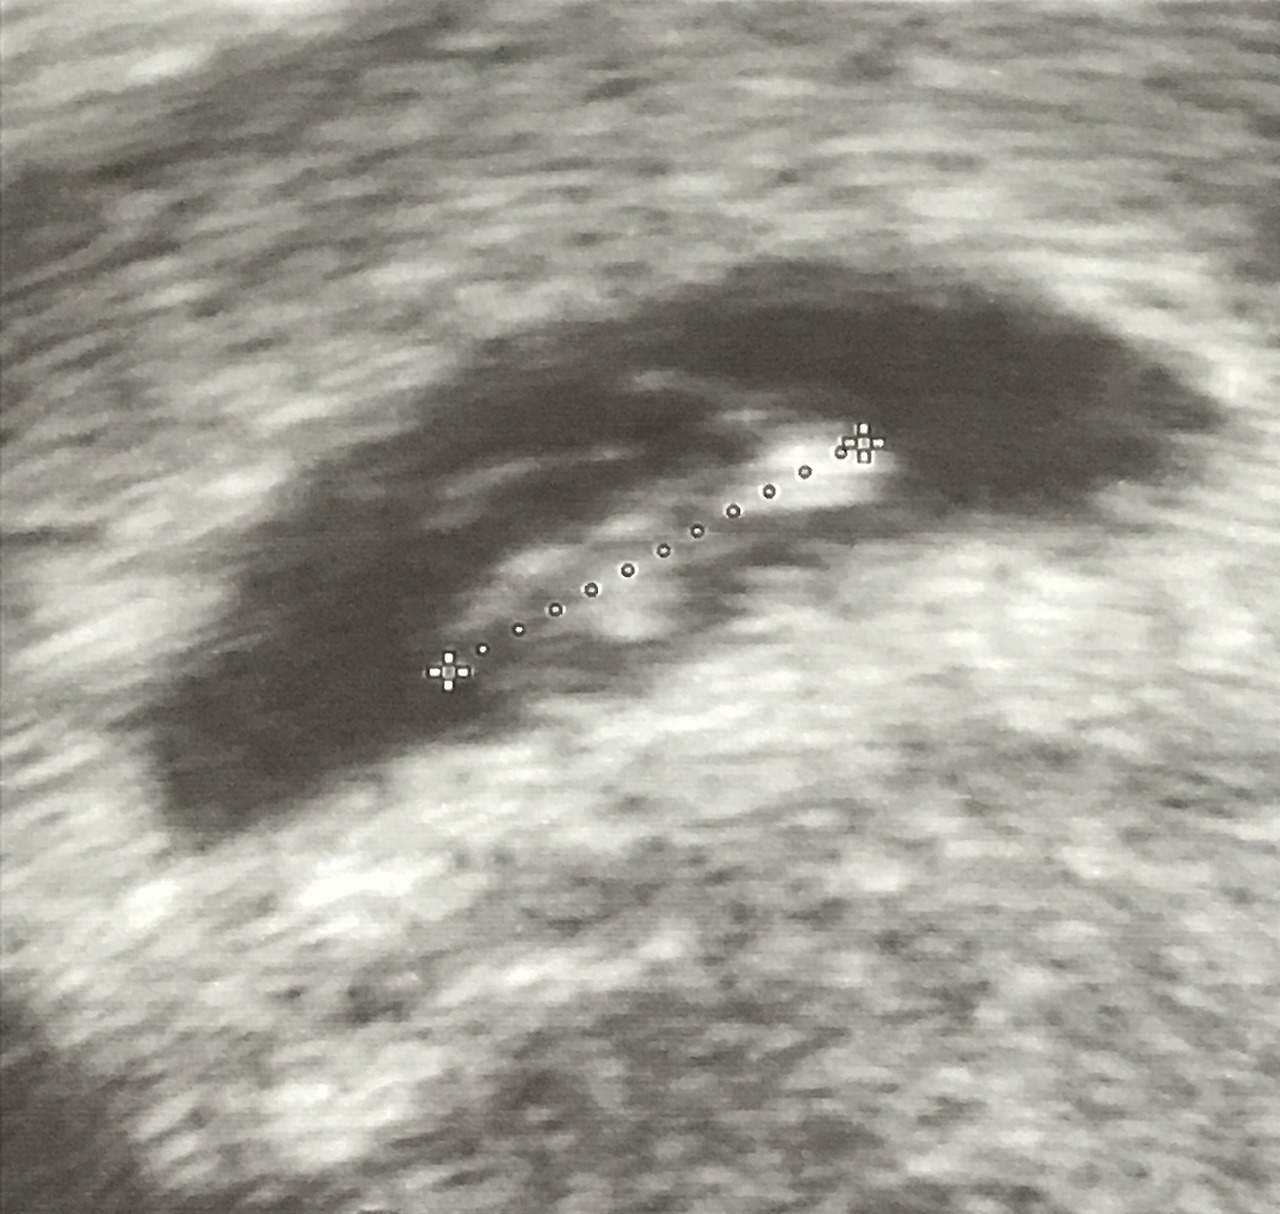

동그란 것이 두개 붙어 길쭉하게 자란 모습이 눈에 띄었다. 하나는 머리고 하나는 몸통이란다. 몸통에 이쑤시개 같이 얇은 기둥 몇개가 데롱데롱 매달려 있다. 이 것이 팔과 다리란다. 머리 엉덩 길이가 대략 1cm정도. 7주차에 적당하게 잘 자라고 있다고 했다. 1cm라니.. 그 길이에 팔과 다리도 달려있다. 초음파 상으로 움직임이 느껴지진 않았지만, 모습을 보는 것만으로도 가슴이 벅차올랐다.

7주차 초음파 사진. 약 1cm 정도로 자란 귤이.